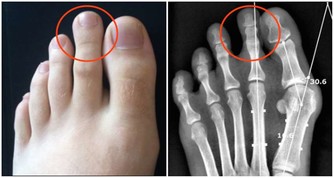

膝關節壽命只有60年,磨損不可修復

關節的壽命是有限的。一旦關節“氣數已盡”,就會引發各種關節病!關節的壽命主要是由基因決定的,一般的健康壽命是60年。